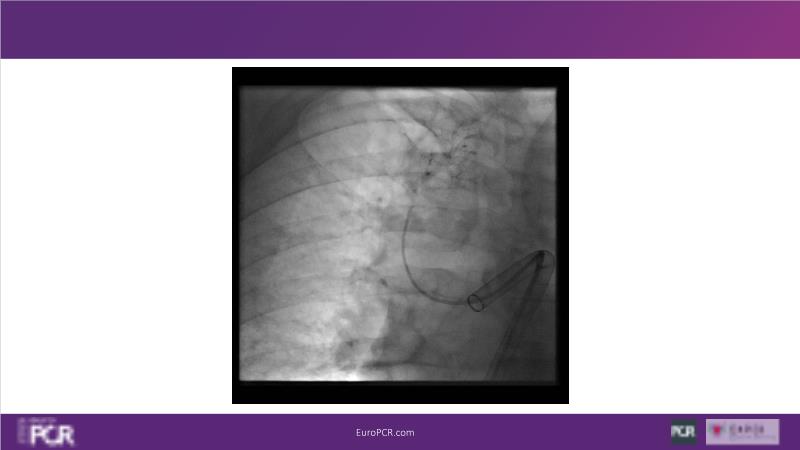

Why mechanical thrombectomy should be considered in the management of acute pulmonary embolism

In this EuroPCR 2024 session, study the case of a patient with high-risk pulmonary embolism and another with intermediate to high-risk pulmonary embolism, delve into discussions on clinical evidence for mechanical thrombectomy in pulmonary embolism, acquire skills to evaluate eligibility for mechanical thrombectomy, and learn how to integrate such technique in local pulmonary embolism patient pathway.